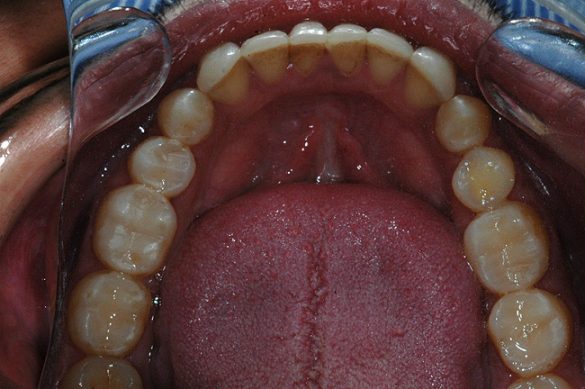

Toţi dinţii posteriori au fost reabilitaţi cu restaurări directe pe bază de răşină şi la nivelul hemiarcadei controlaterale, într-un mod similar celui descris anterior, restabilind astfel dimensiunea verticală (fig. 10, 11). S-a efectuat ajustarea ocluzală şi proximală, pentru a obţine contururi adecvate.

S-a restabilit ghidajul anterior prin înălţarea cu aproximativ 2mm a muchiei incizale la dinţii mandibulari frontali (de la canin la canin). S-a efectuat restaurarea caninului 2.3. impusă de forma necorespunzătoare a acestuia. S-au folosit aceleaşi culori şi materiale şi pentru restaurarea dinţilor frontali (fig. 12). S-a creat o nouă gutieră ocluzală pentru a ajuta la asigurarea unei bune longevităţi clinice. Pacientul a beneficiat de instructaj de igienă orală.